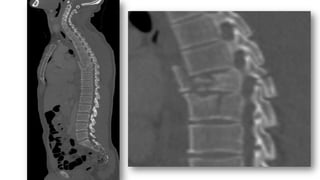

• Lesiones similares en dorsal y en lumbar.

• La mayoría 2/3 desde D12 –L2.

FX DORSOLUMBARES

• 75%. Fx flexión-compresión axial

• Estables

• Múltiple Fx en distintos niveles,

se asocian a FX con estallido en

un 50%

• Perdida de altura sólo, no se

puede distinguir Fx aguda ó

crónica

FX DORSOLUMBARES (CONT)

• Acuñamiento ó depresión del platillo superior del

cuerpo vertebral +/- rotura de la línea post.

• Elementos posteriores están intactos

• Puede haber fragmentos óseos en el canal

raquídeo

• Indicado el TC para valorar el canal pq hay deficit

neurológico en un 65%